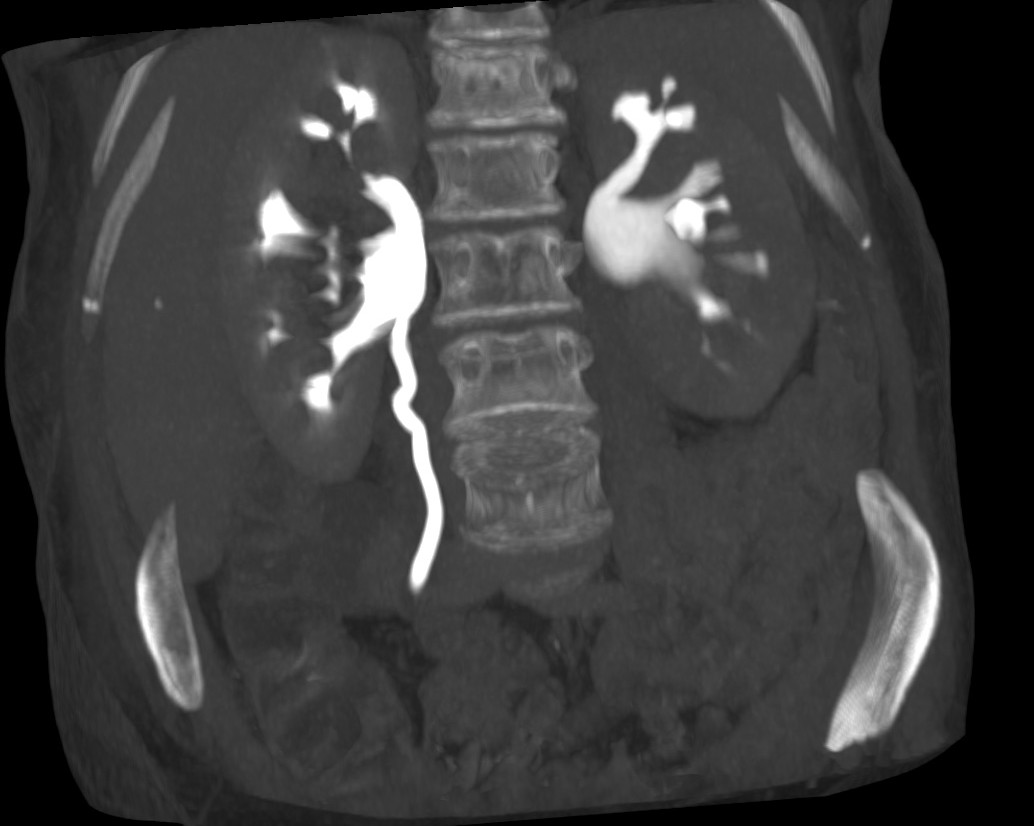

Se procede a realizar TC abdomino-pélvico con contraste en fase nefrográfica y excretora:

Conclusión: se nos presentó un caso de un paciente con una sospecha de infección renal complicada ya que tras cuatro días de tratamiento antibiótico no hubo mejoría. Ante los hallazgos observados en TC, podemos establecer el diagnóstico de pieloureteritis renal izquierda con signos de hidroureteronefrosis leve hasta vejiga.

B- Con el TCMD con contraste en fase excretora podemos estudiar las vías de manera más prescisa y hacer reconstrucciones. Estudio normal.

C- UIV de una hidroureteronefrosis izquierda leve (grado II/IV) hasta vejiga.

- Protocolo: TC abominopélvico sin y con contraste en fase nefrográfica (70 seg) +/- fase tardía ( a los 7 – 10 min) solo si se sospecha obstrucción.

- TC con contraste: Las áreas afectadas del parénquima aparecen como zonas con baja atenuación debido al edema. Las áreas hiperdensas son menos frecuentes y corresponden a focos de hemorragia. Estos hallazgos son mejor valorables a través de la aplicación de contraste, ya que un TC en vacío pueden pasar desaprecibidas.